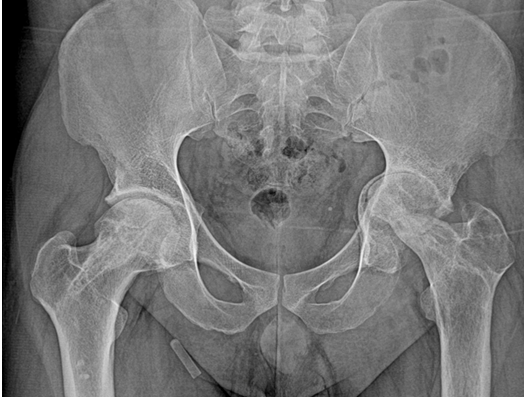

Case Report on Steroid-induced Bilateral Femoral Head Osteonecrosis with Concomitant Hip Septic Arthritis in Primary Membranous Nephropathy

James C George , Manish Tripathi , Jerry Jimmy Chiramel , Ranjana Jayan

………………………………p.75-79